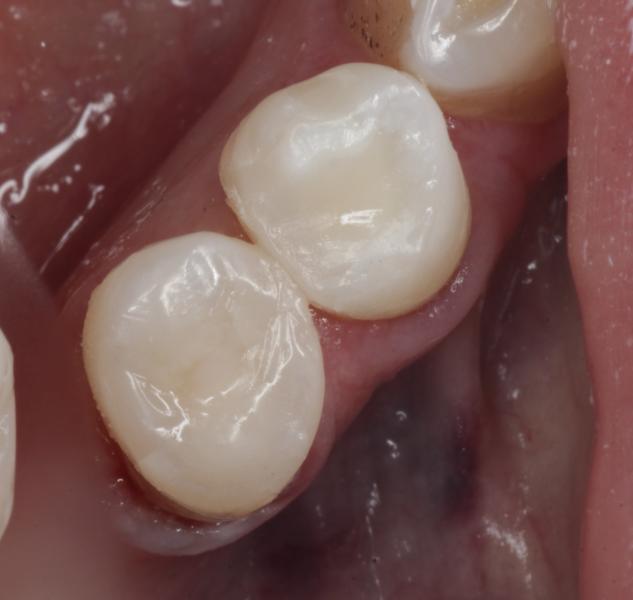

Возрастная пациентка

Лечение кариеса/ пульпита